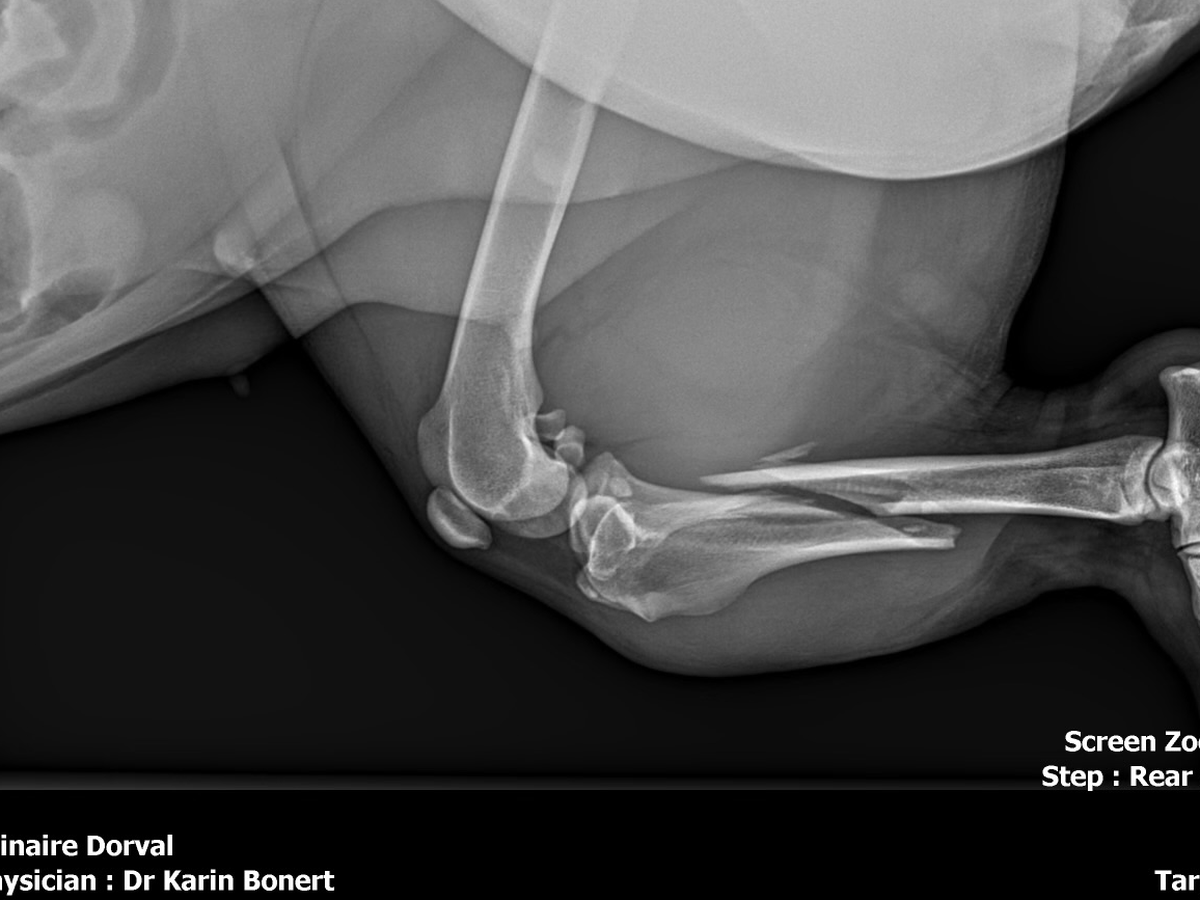

Recently, Shadow and I were involved in a terrible car accident that changed everything in an instant. Despite taking every possible precaution to keep her safe in the car, Shadow suffered a devastating injury and broke her leg. Seeing her in pain has been one of the most heartbreaking experiences our family has ever faced.

We rushed her to the vet immediately and did everything we could. We’ve already paid $1,000 for an emergency cast to stabilize her leg, but we were then told that she urgently needs surgery to properly heal. The cost of this surgery is $8,000, an amount we simply cannot afford on our own after everything we’ve already been through.